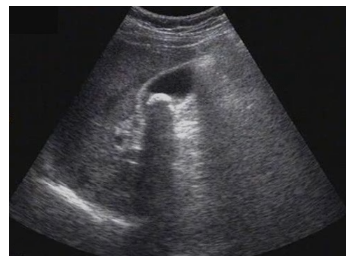

試題3:患者女性,50歲,間斷上腹隱痛半年,診斷為(2分)

A.肝癌

B.肝硬化

C.膽囊結(jié)石

D.腎結(jié)石

E.急性膽囊炎

【答案】C

影像學(xué)3